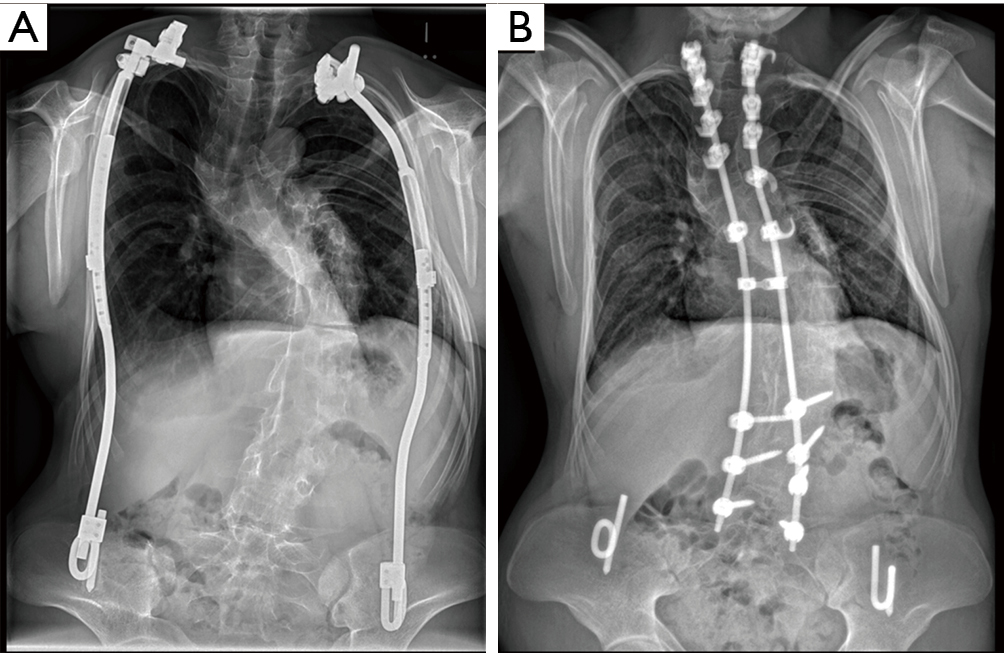

From atm.amegroups.com

Long term of vertical expandable prosthetic titanium rib Titanium Rods In Back Surgery Weight Spinal fusion typically works for fixing broken bones, reshaping the spine or making the spine more stable. The weight of the hardware is. Spinal fusion is a surgery procedure that reinforces your back structure and stability by linking two vertebrae together. But study results are mixed when the cause of the back or neck pain is. The larger diameter rods. Titanium Rods In Back Surgery Weight.